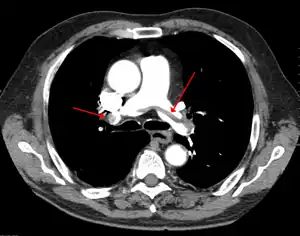

Embolia pulmonar, também conhecida como tromboembolismo pulmonar (TEP), é o bloqueio da artéria pulmonar ou de um de seus ramos. Geralmente, ocorre quando um trombo venoso (sangue coagulado de uma veia) se desloca de seu local de formação e viaja, ou emboliza, para o fornecimento sanguíneo arterial de um dos pulmões.[1] Os sintomas podem incluir falta de ar, dor torácica na inspiração e tosse com sangue.[2] Sintomas de trombose venosa profunda em membro inferior também podem estar presentes, como hiperemia, calor, inchaço e dor.[2] Os sinais clínicos incluem baixa saturação de oxigênio sanguíneo, respiração acelerada e taquicardia. Casos graves de embolia pulmonar não tratada podem levar a perda de consciência, instabilidade circulatória e morte súbita.[3]

Os fatores de risco para a ocorrência de trombose venosa profunda são o câncer, períodos prolongados de repouso no leito, tabagismo, acidente vascular cerebral, algumas doenças genéticas, gravidez, obesidade e alguns tipos de procedimentos cirúrgicos.[4] Uma pequena parcela dos casos podem se desenvolver a partir da embolização de ar, gordura ou líquido amniótico.[5][6] O diagnóstico baseia-se em sinais e sintomas em combinação com exames complementares. Se o risco for baixo, um exame de sangue conhecido como Dímero D pode descartar a condição. Caso contrário, exames de tomografia computadorizada, cintilografia pulmonar ou ultrassonografia de membros inferiores podem confirmar o diagnóstico.[3][7]